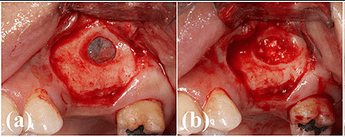

Case photos provided by: Polycaprolactone Impregnated 3D Printed Nanohydroxyapatite for Sinus Augmentation: A Randomized Controlled Trial

Clinical photographs of the surgery. (a) A bony access window was created on the lateral wall of the maxillary sinus. (b) 3DPHA‐PCL was filled in the sinus after detaching the sinus membrane. (c) A collagen membrane was applied to cover the access window. (d) Dental implants were placed on #15 and #16 areas. (e) A bone core biopsy was performed during drilling. (f) The obtained specimen. (g) An implant prosthesis was delivered (#17 was extracted).